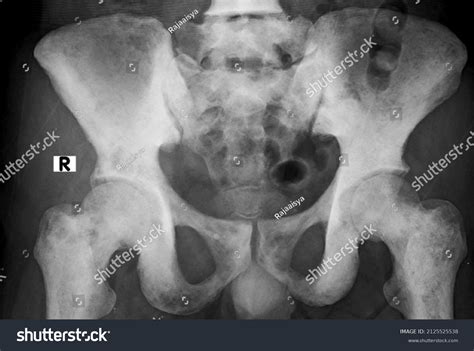

Now, let’s talk about why bone scans are so darn important when it comes to detecting bone metastasis on bone scan . You might be thinking, “Can’t they just do an X-ray?” Well, X-rays are great for showing major breaks or changes in bone density, but they often can’t pick up the subtle changes that happen in the very early stages of bone metastasis. This is where the bone scan shines! Think of a bone scan as a super-sensitive detector. It uses a small amount of a radioactive tracer, usually Technetium-99m MDP. This tracer travels through your bloodstream and is absorbed by bones. Bone is constantly remodeling itself – breaking down old bone and building new bone. When cancer cells invade the bone, they trigger an accelerated process of bone breakdown and rebuilding in that specific area. The radioactive tracer is taken up more readily by these areas of increased bone activity. So, the ‘hot spots’ that show up on the scan indicate areas where there’s more metabolic activity – and in the context of cancer, this often means metastasis. It allows doctors to see the entire skeleton at once, catching any spots that might be missed by other imaging methods. This comprehensive view is absolutely vital for staging the cancer and determining the best course of treatment. Without this detailed map provided by the bone metastasis on bone scan , doctors might be working with incomplete information, which could lead to less effective treatment strategies. So, yeah, bone scans are a pretty big deal in the world of cancer diagnostics, especially when dealing with potential spread to the bones.

This is the part where we talk about interpreting the results of your bone metastasis on bone scan . It’s a bit like being a detective, piecing together clues from the images. The radiologist, a doctor who specializes in reading medical images, will carefully examine the scan. They’re looking for ‘hot spots’ – areas that have taken up more of the radioactive tracer than the surrounding bone. These hot spots can indicate areas of increased bone activity. Now, here’s a crucial point: not all hot spots mean cancer . There are other conditions that can cause increased bone activity, such as arthritis, infections, recent fractures, or areas where bone has been surgically altered. That’s why the radiologist doesn’t just look at the scan in isolation. They’ll consider your medical history, any symptoms you’re experiencing, and results from other tests, like biopsies or other imaging studies. If the hot spots are in locations consistent with cancer spread, and if there are multiple such spots throughout the skeleton, it strongly suggests bone metastasis. The report from the radiologist will detail the location, number, and appearance of any suspicious areas. Your oncologist (your cancer doctor) will then review this report along with all your other medical information to make a diagnosis and develop a treatment plan. It’s a collaborative effort, and understanding these results is a key part of your journey. Don’t hesitate to ask your doctor questions about what the bone metastasis on bone scan shows – it’s your body, and you have the right to understand what’s going on.